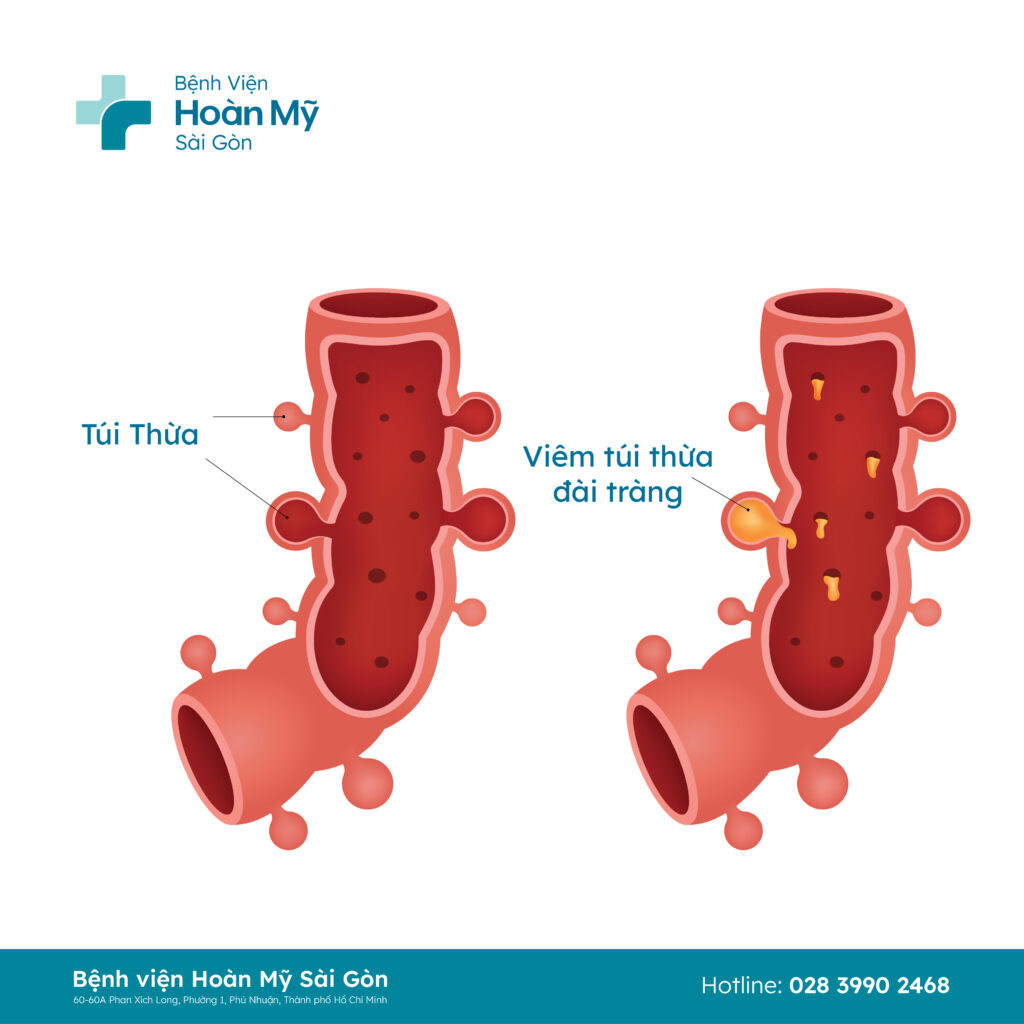

BS.CKII. Nguyễn Thanh Thoại - khoa Ngoại tiêu hóa bệnh viện Hoàn Mỹ Sài Gòn cho biết, viêm túi thừa đại tràng là bệnh lý đường tiêu hóa phổ biến, lúc này ruột có những nơi phình ra như một chiếc túi gây viêm. Triệu chứng bệnh thường không rõ ràng, tiềm ẩn nhiều nguy cơ xuất hiện các biến chứng nguy hiểm như áp xe, viêm phúc mạc, thủng túi thừa, xuất huyết, rò các cơ quan lân cận,...

Ảnh minh họa túi thừa đại tràng

Theo BS. Thoại, túi thừa của ruột đa số không có triệu chứng. Các phương pháp điều trị nội khoa có thể áp dụng và đạt hiệu quả đối với trường hợp viêm nhẹ. Tuy nhiên, nếu viêm nhiễm tiến triển nghiêm trọng có biến chứng, người bệnh sẽ được chỉ định thực hiện phẫu thuật để xử lý.